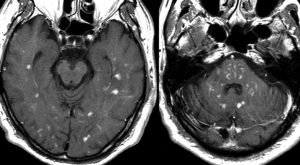

矢印の所を定位脳手術で取りました。病理の結果がリンパ腫と確定されましたから,MTX化学療法をしてから放射線をあてたら,右側のMRIのように腫瘍は消えました。患者さんの症状は良くなって退院したのですがーー。

左から,1回目の再発,2回目の再発,3回目の再発です。再発するたびになんとか治療はできるのですが,違った場所に再発してきてだんだん治療が効かなくなってくることが多いです。このような現象から,脳のリンパ腫は脳に発生するのではなくて,体のどこかに原発巣があるのではないかという考えもあります。もちろん、こんな再発をしないで治ってしまう患者さんも多いです。